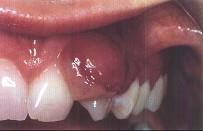

问题 妊娠瘤的临床表现是 ( )

选项 A.多发生于多个牙的牙间乳头 B.以下前牙区唇面龈乳头多见 C.生长慢,质地坚韧 D.疼痛明显 E.妊娠期不能手术切除妊娠瘤

答案 B